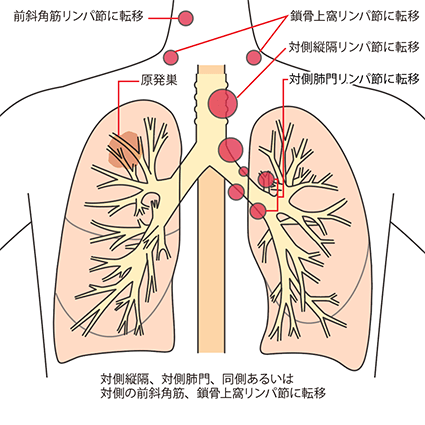

N3

対側縦隔、対側肺門、同側あるいは対側の前斜角筋、鎖骨上窩リンパ節への転移

N3は、原発巣とは反対側の縦隔リンパ節や肺門リンパ節または鎖骨上のリンパ節、首の付け根にあるリンパ節に転移があることです。

IIIB・IIIC期(ステージ3):局所進行がん

TNM分類でⅢB・ⅢC期と分類された肺がんは、ⅢA期よりさらに進行した状態の局所進行がんとされています。原発巣側の肺外にリンパ節転移が生じています(N2またはN3)。手術ですべてを取り切ることは難しく、手術をしてもがんが残ってしまう可能性が高いことから、基本的に手術はおこないません。

IIIB期

TNM分類でⅢB・ⅢC期と分類された肺がんは、ⅢA期よりさらに進行した状態の局所進行がんとされています。原発巣側の肺外にリンパ節転移が生じています(N2またはN3)。手術ですべてを取り切ることは難しく、手術をしてもがんが残ってしまう可能性が高いことから、基本的に手術はおこないません。